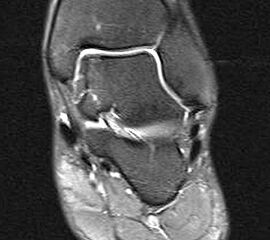

Abbildung 1: Osteochondrale Läsion der medialen Talusschulter mit subchondralem Begleitödem und Zyste.

Abbildung 1

• MRT des Sprunggelenks zur Beurteilung der Knorpelläsion, möglichen subchondralen Zysten, nekrotischen Knochenarealen und anderen Begleitpathologien (Abbildung 1).

Die Darstellung der weiteren Operationstechnik erfolgt am Beispiel eines medialen Zugangs bei einer Osteochondrosis dissceans mit subchondraler Zyte der medialen Talusschulter (siehe MRT Abbildung 1).